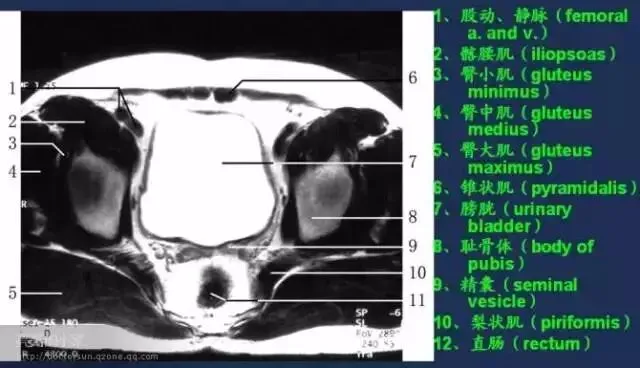

收藏!全身MRI解剖图谱,医生必备